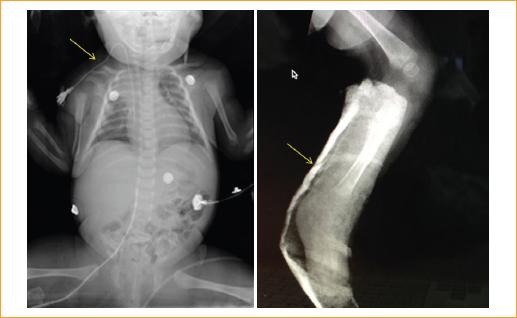

El motivo de consulta de los pacientes fue por crisis convulsivas en 6 (83.3%). Otros síntomas que obligaron a acudir al hospital fueron dificultad respiratoria, rechazo al alimento, llanto inconsolable persistente, vómito, somnolencia y pérdida de la conciencia (Tabla 2 , Figs. 1 y 4).

Figura 1 Paciente en coma barbitúrico con sospecha de trauma craneal abusivo, lesión con impresión de arcada dentaria en la pierna derecha.

Entre los hallazgos de la exploración clínica encontramos que cuatro pacientes (50%) presentaron fracturas en distintas localizaciones: en el cráneo dos pacientes (uno en la región parietal derecha y otro en la región parietooccipital), un paciente presentó fracturas en cuatro costillas, uno más presentó una fractura clavicular, y uno más tibiales y acromiales, todas ellas diagnosticadas por estudios radiológicos (Tabla 4, Figs. 2 y 3).